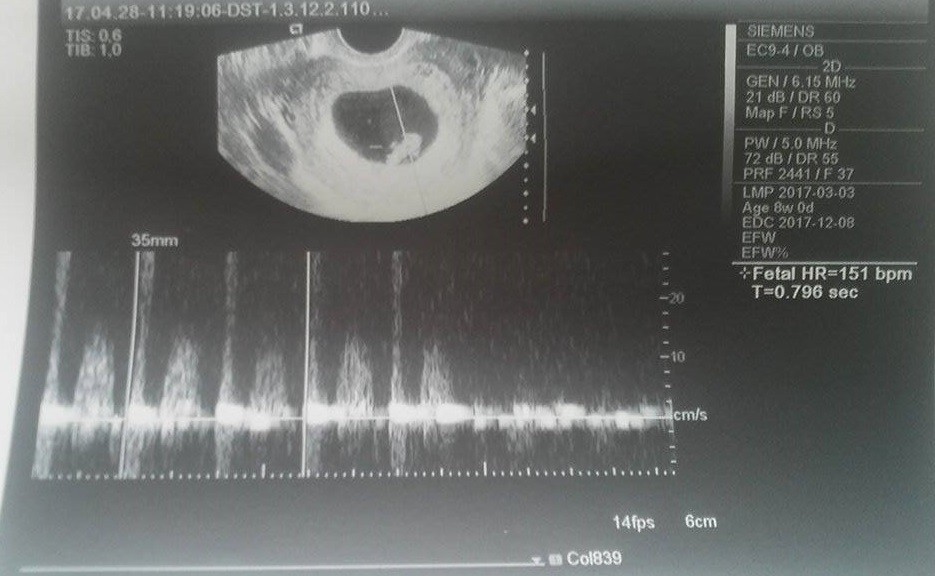

A to jest nasz Dziedzic :)

Hej, była obsuwa, właśnie skończyłam wizytę. Chyba zaraz latać zacznę :) Maleństwo sporo urosło i jak wcześniej było o 3 dni młodsze niż wg OM, to teraz o 1 dzień starsze, czyli 8t1d ;) Widziałam i słyszałam serduszko, yupii. Tylko lekarz mi nie dał zdjęć :( ale za to pozwolił cyknąć fotkę jak bardzo poprosiłam. Teraz termin mi się przesunął na 8.12 ciekawe jak to ostatecznie będzie... Sorki że tak chaotycznie ale cała w skowronkach jestem, kolejna wizyta 17.05, a do tego czasu reszta badań.

Zobacz załącznik 804346 Zobacz załącznik 804347 Zobacz załącznik 804348